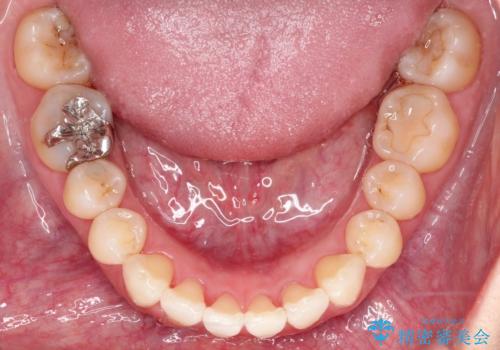

- 前歯の凸凹と、前突を主訴に来院されました。

インビザライン にて治療を行なっております。

治療期間中はゴムかけを行なってもらうことで、前歯を下げることができました。